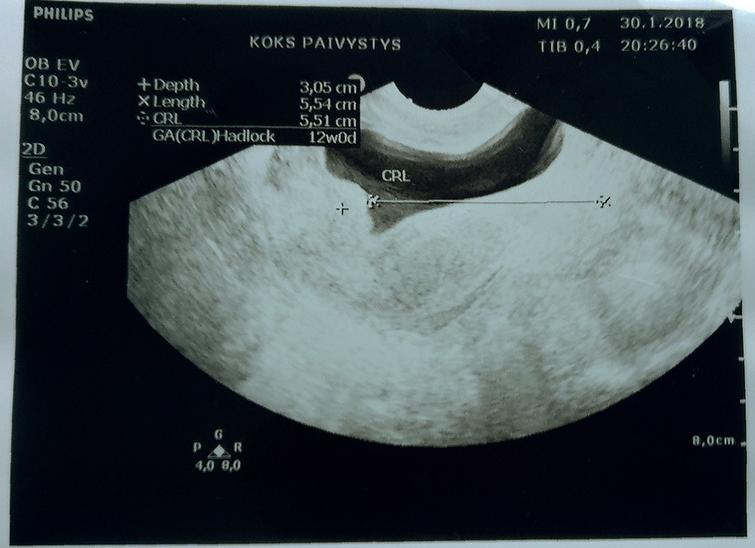

Если падает ХГЧ, почему это происходит, сможет сказать только квалифицированный врач. После оценки результатов анализа он назначит дополнительные диагностические процедуры, в том числе и УЗИ. В дальнейшем, исходя из причины нарушения, он предложит максимально эффективное лечение.

Здравствуйте, Алиса! На первых неделях ваша беременность нормально развивалась, о чем можно судить по темпу прироста ХГЧ. Замедление же его роста (когда прирост ниже нормального) свидетельствует об определенном неблагополучии, после чего врач более тщательно наблюдает за беременной. Снижение уровня ХГЧ говорит в пользу прервавшейся или замершей беременности. И в таком случае уже спасти нечего. В таком случае женщине показано УЗИ для контроля состояния плода. Если беременность замерла, по необходима чистка или вакуум-экстракция плода (зависит от срока). В вашем случае возможно два варианта. Беременность действительно могла замереть или прерваться или же вы получили ошибочные лабораторные данные — такое тоже бывает. На сегодняшний день вам предпринимать ничего не стоит. Самостоятельно принимать дюфастон нет смылсла. Если произошла ошибка в лаборатории, то беременность нормально развивается и ничего не требуется. Если плод замер, то ситуацию уже, к сожалению, ничем не поправить. Пойдите к своему гинекологу и на УЗИ. Ели у врача возникнут сомнения, то он вам назначит повторный визит через неделю для оценки состояния плода в динамике. Но в таком случае делайте УЗИ у одного и того же врача на том же аппарате.

Трактовать результат обязательно должен врач, учитывая данные УЗИ и другие лабораторные показатели.

Самым информативным методом, позволяющим узнать больше о протекании беременности, является УЗИ.